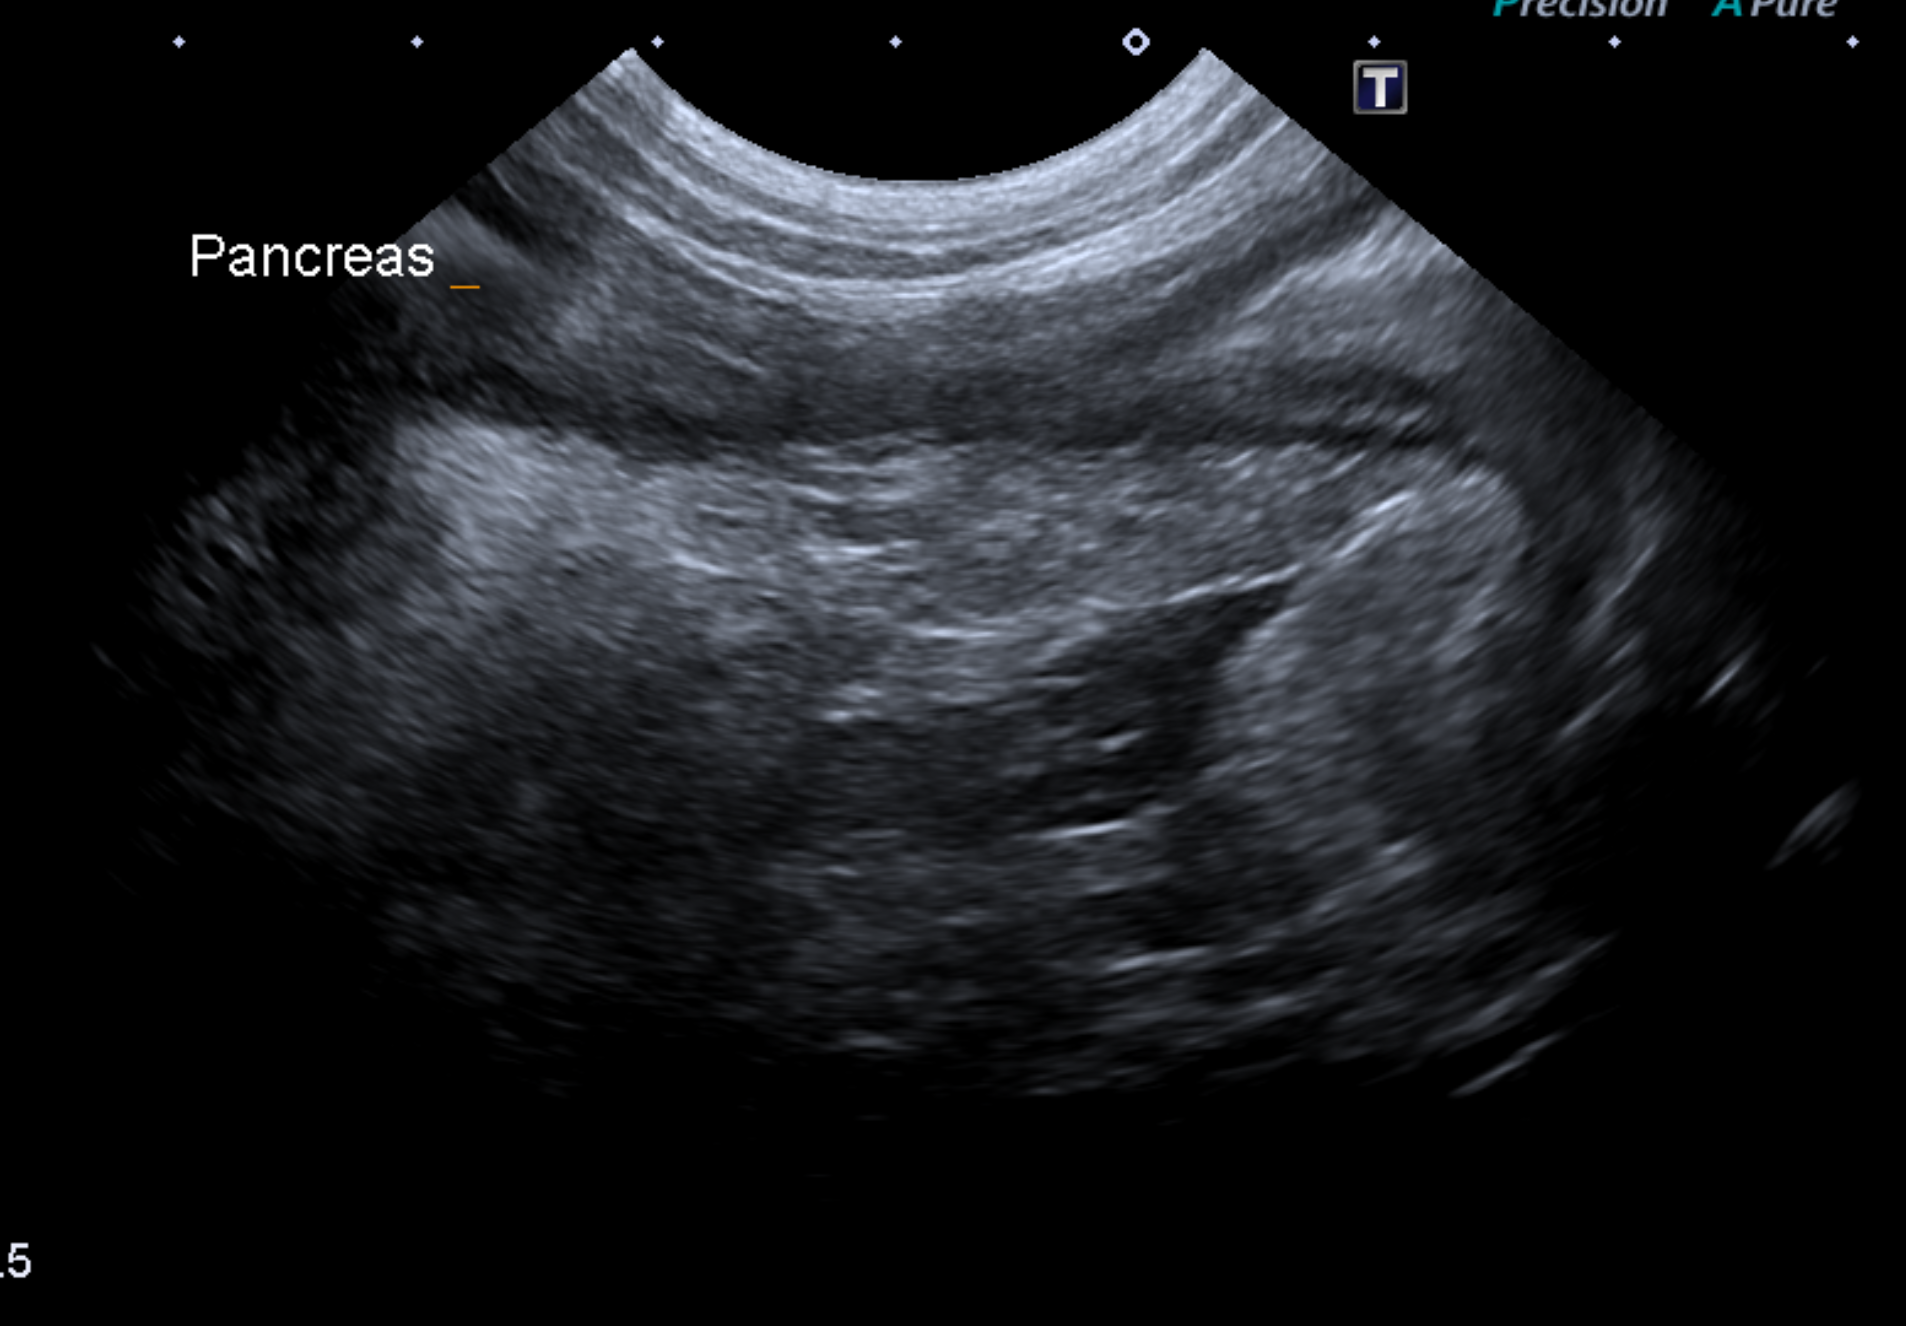

血液検査では膵臓から分泌されるLIP (リパーゼ)値上 昇、炎症があるときに上がるCRPの上昇が見られることが多いです。また、外部への依頼検査で、確定 診断として犬特異的膵リパーゼ(c-PLI)を測定する こともあります。 超音波検査では膵臓の腫大・膵臓周囲の高エコー源 生・十二指腸まで炎症が波及することによる十二指腸のコルゲートサイン(うねうねしてみえる)が指 標となります。

膵臓が炎症により高エコーとなりモヤモヤして見えるのが分かります。